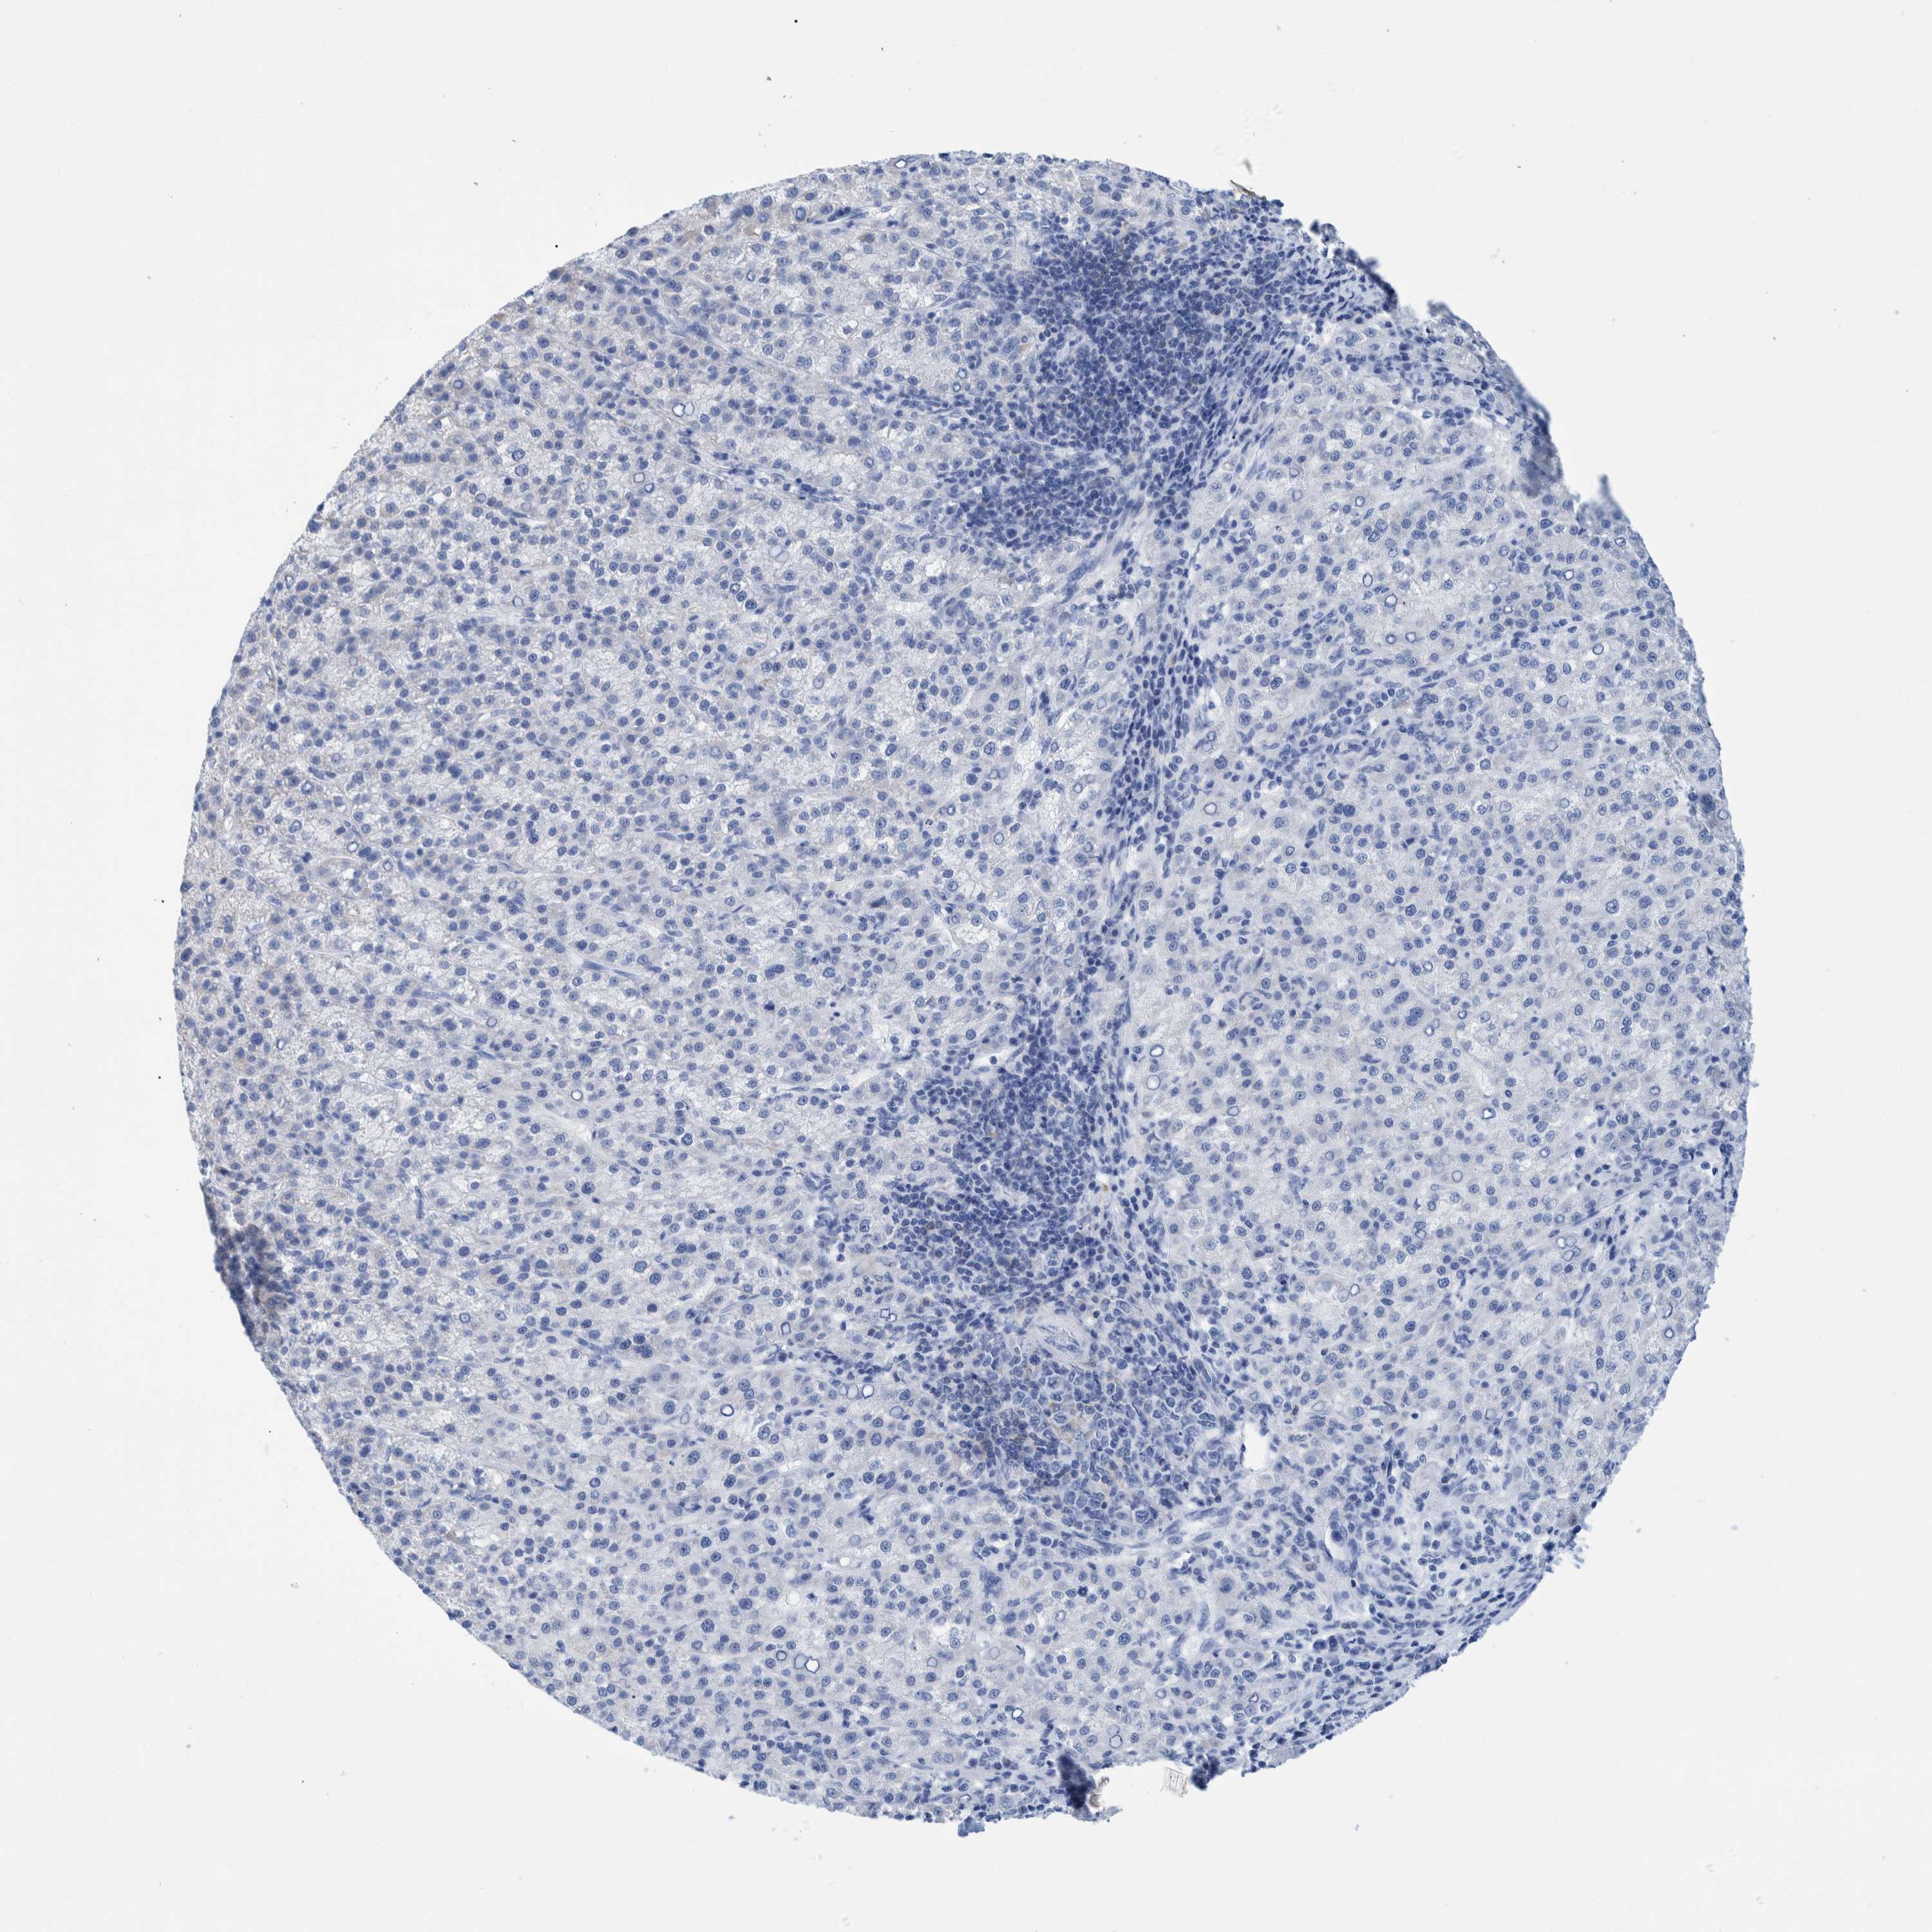

LIVER CANCER - Protein expressioni

A mouse-over function shows sample information and annotation data. Click on an image to view it in a full screen mode. Samples can be filtered based on level of antibody staining by selecting one or several of the following categories: high, medium, low and not detected. The assay and annotation is described here.

Note that samples used for immunohistochemistry by the Human Protein Atlas do not correspond to samples in the TCGA dataset.

Antibody HPA000452

Antibody HPA023040

Antibody CAB000134

Staining

High

Medium

Low

Not detected

Intensity

Strong

Moderate

Weak

Negative

Quantity

>75%

75%-25%

<25%

None

Location

Nuclear

Cytoplasmic/membranous

Cytoplasmic/membranous,nuclear

Carcinoma, Hepatocellular, NOS

Cholangiocarcinoma